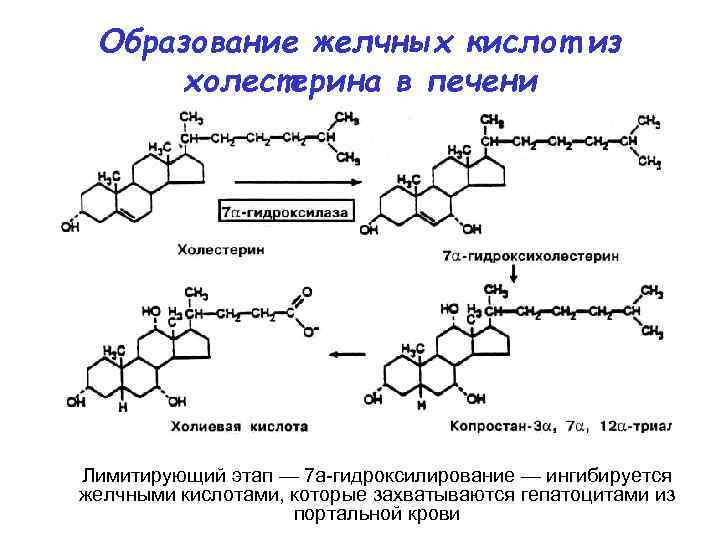

Образование желчных кислот из холестерина в печени Лимитирующий этап — 7 а-гидроксилирование — ингибируется желчными кислотами, которые захватываются гепатоцитами из портальной крови

Образование желчных кислот из холестерина в печени Лимитирующий этап — 7 а-гидроксилирование — ингибируется желчными кислотами, которые захватываются гепатоцитами из портальной крови